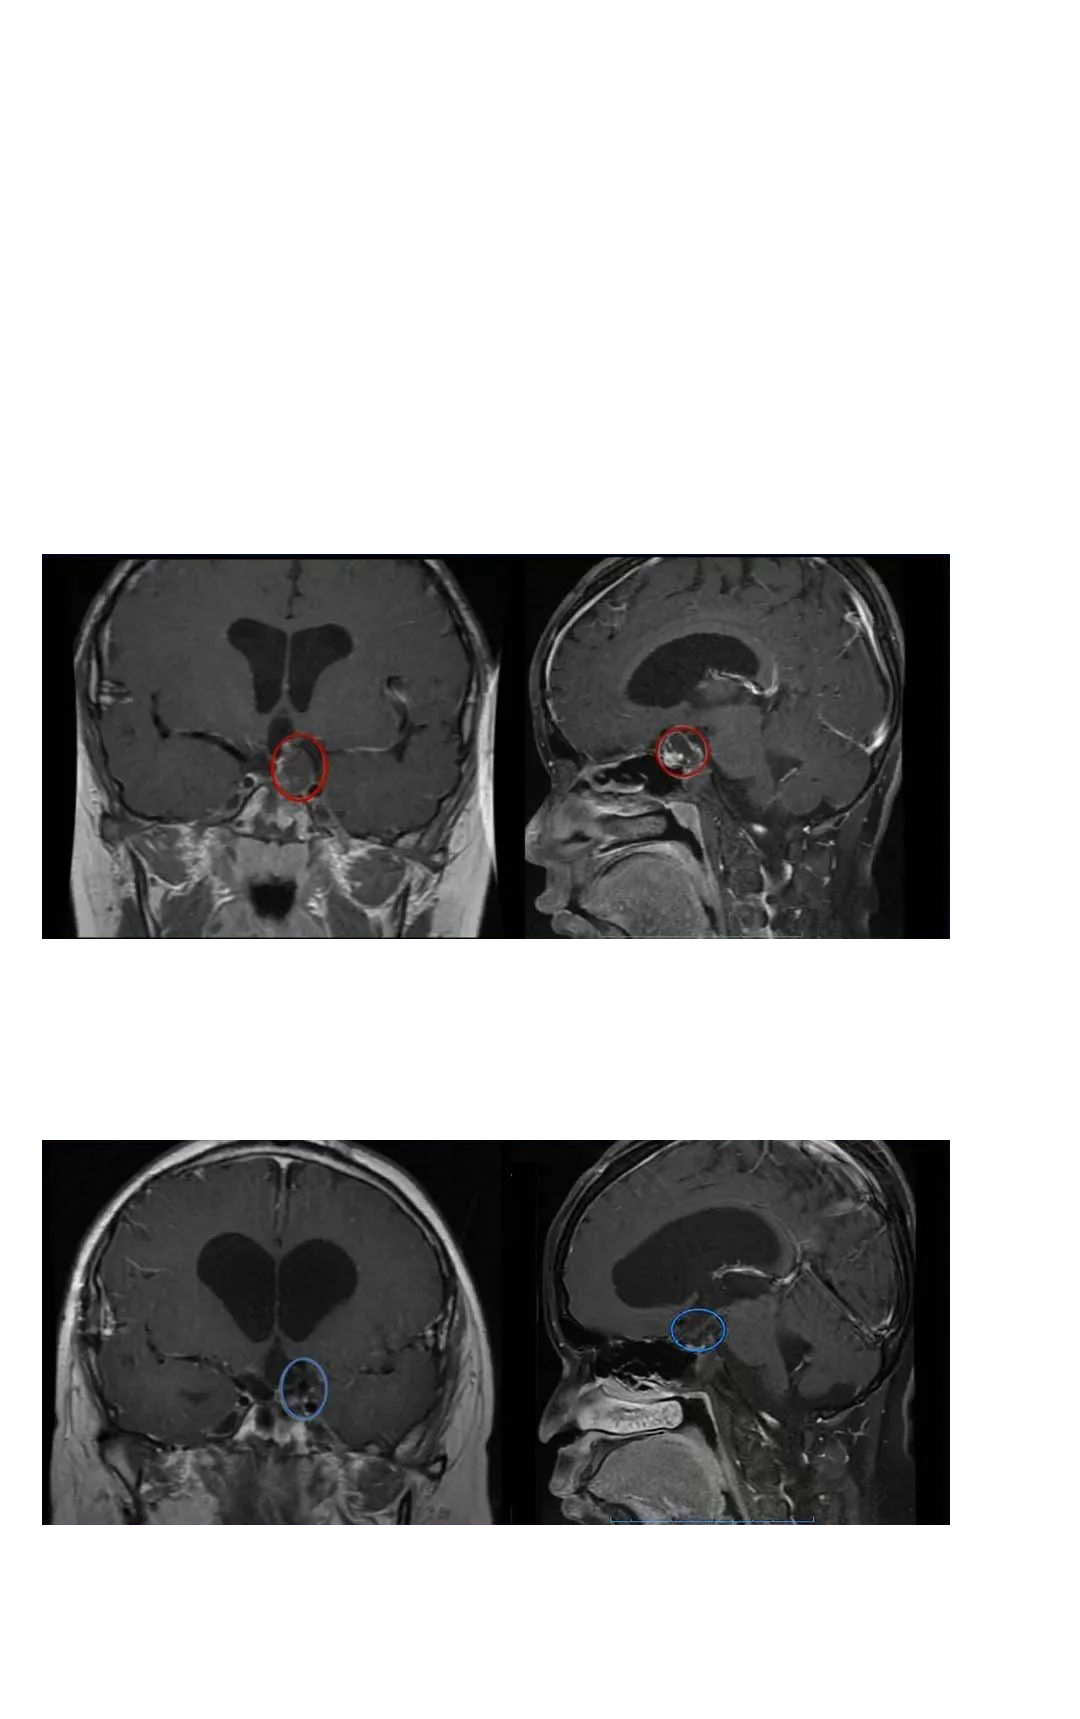

巴特朗菲教授回复:如果采用术中核磁共振成像,那么我可以近乎全切切除肿瘤,手术的目的是去除该区域全部可见的肿瘤部分,术中风险很低。术后可辅助质子治疗控制复发,精确的内分泌管理也是必要的。

巴特朗菲教授在德国INI的术中磁共振复合手术室为小杰顺利进行了手术,肿瘤得到了全切,没有出现任何严重的神经损伤。

小杰的家人再次联系INC,希望由巴特朗菲教授评估一下术后三个月的影像资料,INC巴特朗菲教授很快回复邮件:“我研究了患者2020年5月8日的MRI对照,无肿瘤复发,影像也无明显问题,建议6-8个月再次复查对照。”